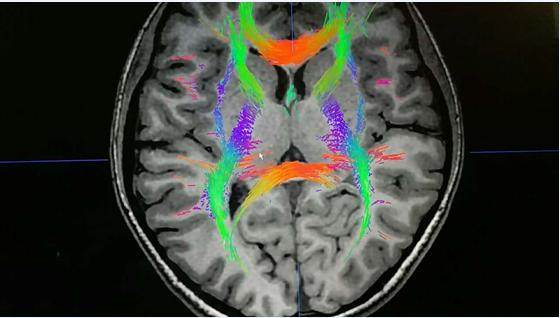

第五代腦立體定向技術(shù)屬于微創(chuàng)神經(jīng)調(diào)控術(shù),主要針對(duì)的患者群體即為難治性精神疾病患者群體。手術(shù)結(jié)合現(xiàn)代醫(yī)學(xué)技術(shù)以及影像學(xué)技術(shù),通過(guò)DTI、MRI、CT等影像學(xué)系統(tǒng)對(duì)患者進(jìn)行多靶點(diǎn)神經(jīng)調(diào)控,神經(jīng)調(diào)控區(qū)遠(yuǎn)離大腦功能區(qū)、智能區(qū)等重要區(qū)域,因此術(shù)后患者的智力、語(yǔ)言、行走、邏輯思維等能力皆可以正常保留。